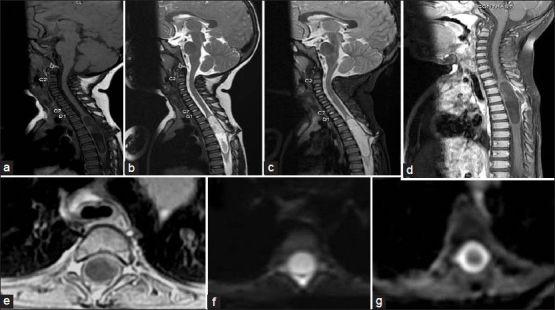

Intramedullary dermoid cyst is a rare entity. It is usually associated with spinal dysraphism and dermal sinus. Our case is an 18-months-old female child who presented with history of fever and mild difficulty in moving left leg. She had a sinus in mid dorsal spine since birth with history of intermittent discharge from it. On magnetic resonance imaging of spine she was diagnosed to have large intramedullary epidermoid/dermoid cyst in the D2-7 vertebral level with a sinus tract. A dermoid cyst along with the sinus tract was excised. Post-operative follow up period was uneventful with full recovery.

髓内皮样囊肿是一种罕见的病症。它通常与脊柱发育异常和皮样窦道相关。我们的病例是一名18个月大的女童,有发热病史且左腿活动轻度困难。她自出生起在脊柱中背部有一个窦道,并有间歇性分泌物排出史。脊柱磁共振成像显示,她在D2 - 7椎体水平有一个伴有窦道的巨大髓内表皮样/皮样囊肿。连同窦道一起切除了皮样囊肿。术后随访期间情况平稳,患儿完全康复。